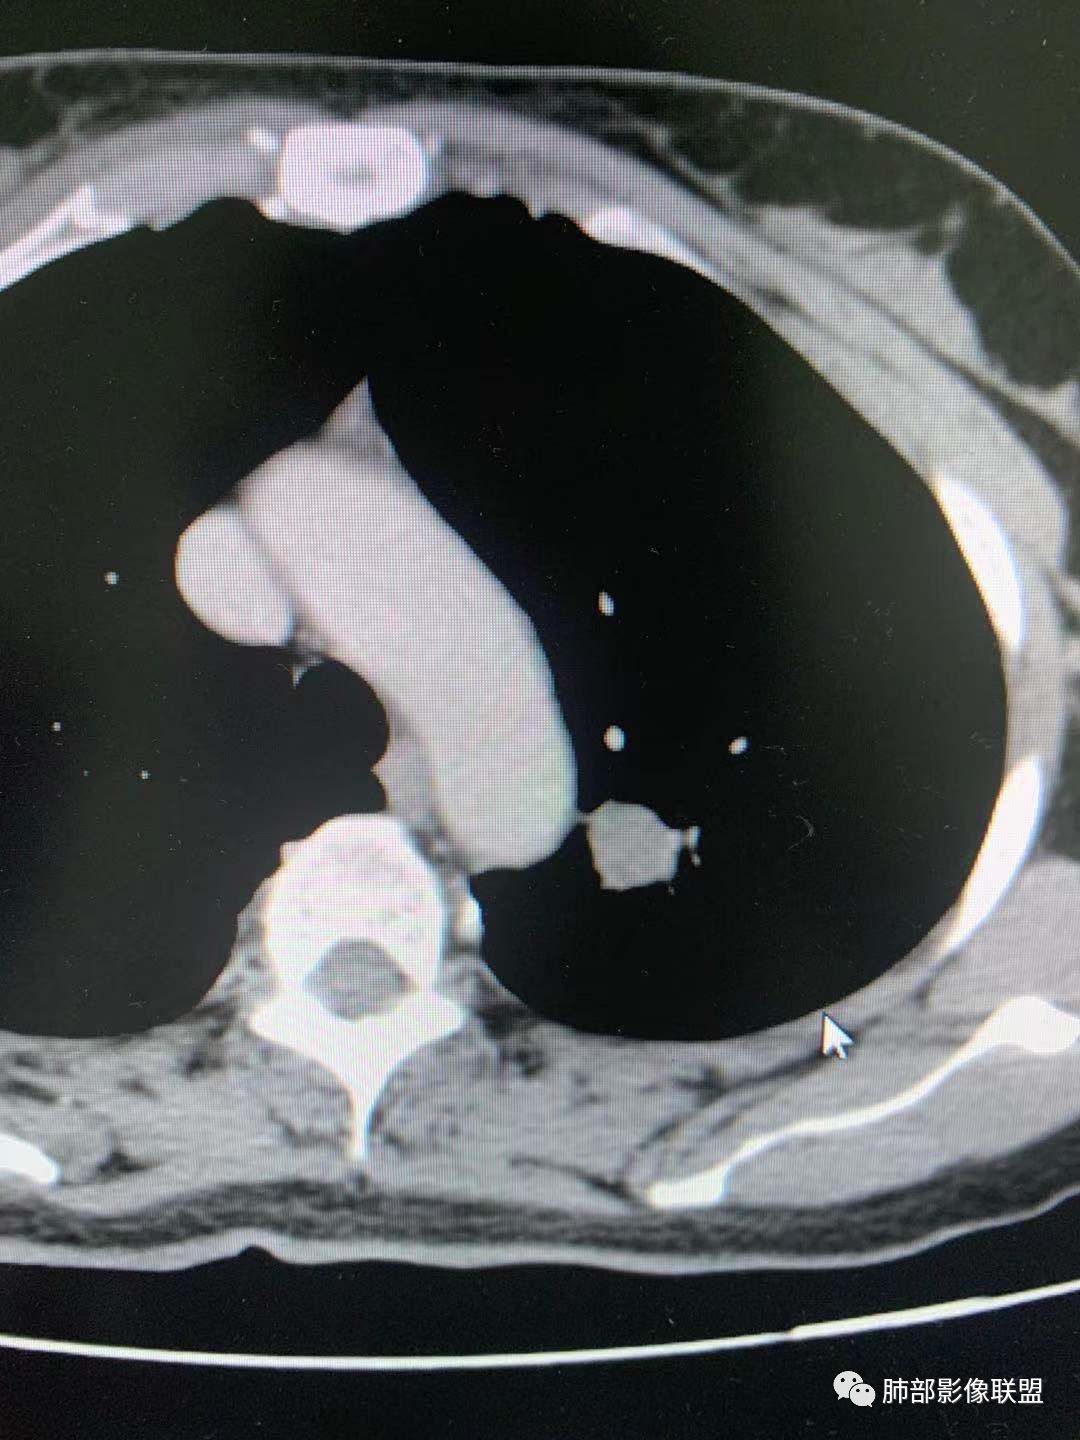

一.尖后段高密度大结节:

1.左肺上叶尖后段较大类圆形实性密度结节影,密度均匀,中等程度强化。

2.实性密度区边缘相当清楚,表面欠光整,偶见毛刺、棘突和旁出血管结构,未见典型的深分叶及邻近胸膜凹陷。

3.可疑支气管进入受阻。可惜缺乏连贯图像或冠矢状位以资判断。

4.病灶与胸膜之间有连线,邻近段支气管及肺血管整体后移,提示病灶还是有一定收缩性。

如上,单就这实性结节,硬化性肺细胞瘤(PSP)和腺癌似乎都能够解释,形态太规整了一些。

5.病灶周围见边界清楚的磨玻璃影,有点醒目,有点意外!

这是无论如何不能忽视的征象!

这点强烈提示,要么整个病灶恶性(腺癌),要么良性病灶旁滋生恶性病灶。

两年前左上肺的病灶什么位置,什么模样,是否相关?我们不得而知。